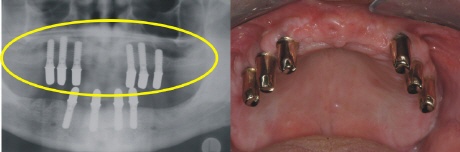

Sechs strategisch günstig positionierte Implantate wurden im Oberkiefer eingebracht, um nach der Einheilung optimalen Halt für die Prothese zu gewährleisten (gelber Kreis im Röntgenbild).

Im Unterkiefer können die vier Implantate (Standardversorgung) im vorderen Kieferbereich eingebracht werden (gelber Kreis im Röntgenbild).